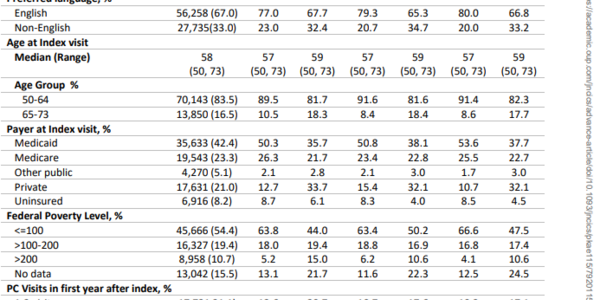

Over 50,000,000 Americans get subsidized or free health under the Affordable Care Act but that doesn't mean usage of preventive care increased across the board. Instead, a new analysis found that the...